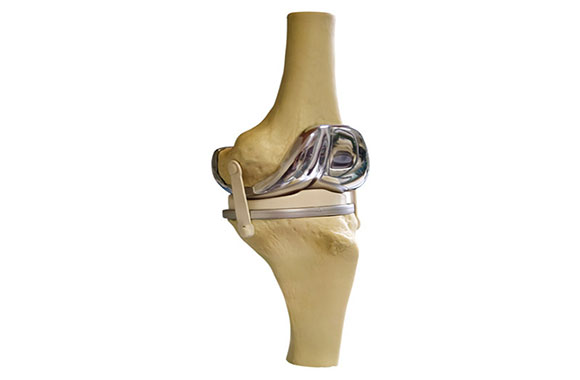

人工関節置換術(膝)

人工関節置換術とは

人工膝関節置換術は、摩耗していたんだ膝の関節面を人工インプラントで置き換える手術を指します。

関節軟骨は円滑に動いているのですが、傷んだ関節表面は削れて欠損していたり、過剰な骨が増生しています。人工関節に置き換えるべき厚みを削って人工関節に置き換えて設置します。

大腿骨、脛骨、膝蓋骨といったすべての膝関節の表面を置き換える人工膝関節全置換術(TKA)と、部分的な人工膝関節置換術(UKA)に大別されます。

スポーツについては軽いスポーツ(ゴルフ、卓球、水泳など)は可能です。運動強度が高く負荷も高いスポーツ(マラソンやジャンプを伴う競技)を行う事は勧めません。

画像:Partial knee replacement – series—Aftercare: MedlinePlus Medical Encyclopedia

Knee joint replacement: MedlinePlus Medical Encyclopedia

手術では、麻酔方法は病院により異なりますが、一般的には全身麻酔で患者さんは寝ていることが多いです。

仰向けで膝を曲げて、膝正面またはややカーブする切開を加え、お皿の骨(膝蓋骨)を移動させながら膝を開いていきます。

一般的な内側型のUKAでは膝内側の関節面の骨棘、半月板を切除していき、大腿骨側(太ももの骨)と脛骨側(ふくらはぎの骨)の関節部分を切除していき、人工関節のサイズを適合させて置換します。

ポリエチレンの素材でできた白いインサーターというものを入れて滑らかに動けるようにします。

TKAの手術では、先程のUKAと異なり内側、外側ともに置換できるようになっている人工関節で取り換えていきます。つまり、内側や外側のみの単独の障害ならばUKAが選べるが全体的な障害だったり、靭帯が切れていて不安定な場合などは、TKAを選択していきます。

UKAは1時間程度、TKAでは1-2時間手術にかかることが多いです。

手術後は2週程度で退院となる事が多いです。